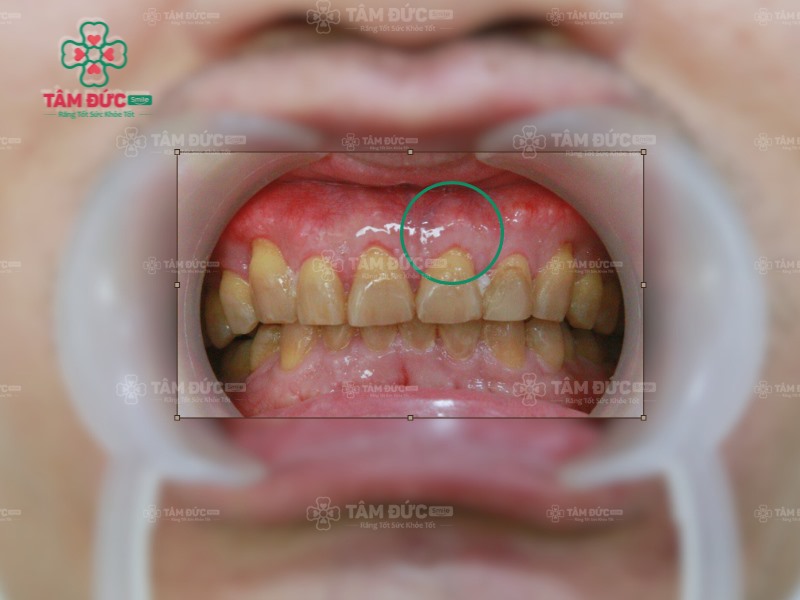

Viêm lợi sưng đỏ nhanh chóng tiến triển thành viêm nha chu